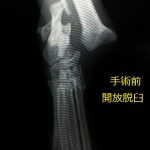

外猫ちゃんが帰ってきて足根関節脱臼を引き起こしていました。

足根関節というのはいわゆるあしくびの部分の関節で、交通事故などの外力により脱臼を引き起こします。

同時に、脱臼だけではなくて、骨が皮膚の外側に出ている、開放骨折(脱臼)を引き起こしていました。